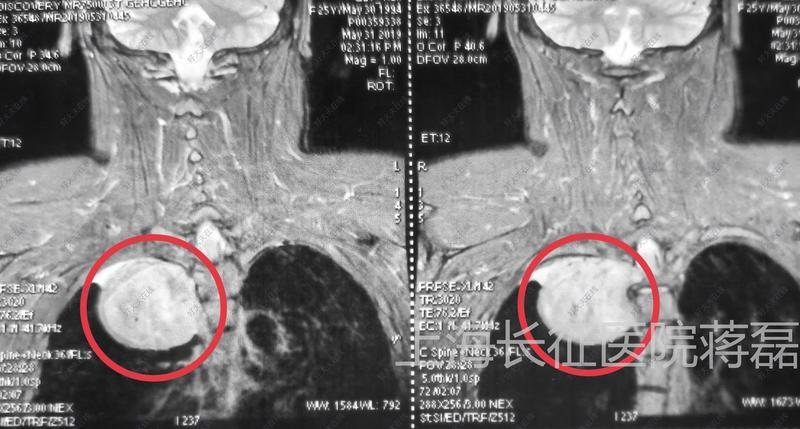

日常生活中,頭痛頭暈是許多人都出現(xiàn)過的癥狀,那么大家會如何處理呢?今年32歲的李先生,也發(fā)生了頭痛頭暈的癥狀。由于發(fā)病突然,頭暈發(fā)作時還伴有行走不穩(wěn)的情況,幾次發(fā)作之后,李先生便前往當?shù)蒯t(yī)院進行治療。經(jīng)過顱腦CT平掃和DSA腦血管造影檢查,結果提示:李先生可能出現(xiàn)了蛛網(wǎng)膜下腔出血的情況,但好在腦實質內沒有出血。而在顱腦右側橫竇乙狀竇區(qū),醫(yī)生卻發(fā)現(xiàn)了異常情況,于是做出了初步診斷:硬腦膜動靜脈瘺。不久,李先生在全麻下接受了硬腦膜動靜脈瘺栓塞術。不過,由于微導管位置不到位,這次介入手術失敗了。為尋求進一步治療,李先生慕名來到上海長征醫(yī)院神經(jīng)外科呂立權教授門診。在進行頭顱MRI平掃+增強檢查后,呂教授在患者的腦右側橫竇乙狀竇區(qū)發(fā)現(xiàn)異常信號,T1WI呈等低混雜信號,T2W2呈高低混雜信號,T1增強呈不均勻強化,周圍腦組織無明顯水腫。MRV檢查提示,患者的右側橫竇乙狀竇完全閉塞,右側頸靜脈未顯影。呂教授詳細分析了李先生的MRI影像學特征,并結合在外院做的DSA檢查結果,認為該患者的診斷不是硬腦膜動靜脈瘺,很可能是右側橫竇乙狀竇區(qū)腦膜瘤。腫瘤位置特殊,位于靜脈竇內,要完整切除腫瘤,需要行開顱手術。右側橫竇乙狀竇區(qū)異常信號,T1WI呈等低混雜信號,T2W2呈高低混雜信,T1增強呈不均勻強化,周圍腦組織無水腫。MRV檢查,右側橫竇乙狀竇閉塞,右側頸靜脈未顯影。手術過程中發(fā)現(xiàn),病灶位于右側橫竇乙狀竇內,竇內充盈飽滿,實性變,無正常引流功能。腫瘤起源于竇內壁,與內壁粘連緊密,無法完全分離。腫瘤血供豐富,質地較韌,部分囊變,囊液呈清亮黃色。于腫瘤與正常橫竇交界處結扎橫竇,在腫瘤遠端靠近頸靜脈球處結扎乙狀竇遠端,將腫瘤連同橫竇乙狀竇一并切除。術后MRI顯示:腫瘤切除滿意,周圍腦組織無出血壞死表現(xiàn)。術后MRI顯示右側橫竇乙狀竇區(qū)腫瘤切除滿意,臨近腦組織無出血壞死。術后病理結果回報顯示:腫瘤組織呈彌漫交織狀排列,瘤細胞呈梭形、卵圓形,胞漿較豐富,核深染輕度核異形,偶見核分裂,未見腫瘤性壞死,間質小血管部分呈分支狀擴張。病理結果考慮為:孤立性纖維性腫瘤(SFTI級)。A.HE染色可見梭形細胞B.信號轉導和轉錄激活因子6(STAT6)陽性。CCD34陽性;D“鹿角”型血管。什么是孤立性纖維性腫瘤?李先生患的是什么病呢?孤立性纖維性腫瘤(SFT)最早于1931年報道于世。一般多發(fā)生于胸膜腔或者全身其他部位,非常罕見的發(fā)生于顱內。近年來研究發(fā)現(xiàn),顱內孤立性纖維瘤(ISFT)和血管周細胞瘤(HPC)在基因表達上有相似性,于是2016年WHO中樞神經(jīng)系統(tǒng)腫瘤分類中便將SFT及HPC合并為同一類腫瘤,即:SFT/HPC。分析顯示,孤立性纖維瘤(SFT)好發(fā)于38-45周歲的中青年人群,且好發(fā)于男性。據(jù)文獻報道,SFT的年發(fā)生率約為0.2/10萬人,而SFT/HPC的發(fā)病率占顱內腫瘤的1.9-4%,發(fā)病率相當罕見。ISFT的發(fā)病位置通常位于與硬腦膜毗鄰的大腦鐮、大腦凸面、小腦幕、后顱窩和橋小腦角區(qū),腦室、鞍區(qū)和海綿竇區(qū)少見。李先生的發(fā)病位置位于橫竇乙狀竇區(qū),呈現(xiàn)為竇內生長,未突破竇腔。這在國內外都未見有相關報道,屬于罕見病例。那么ISFT具有哪些特點呢?據(jù)呂教授介紹,ISFT具有腦外腫瘤的特點,患者可以表現(xiàn)出頭痛、頭暈的癥狀。但是ISFT被纖維包膜包裹,與周圍腦組織之間有較為清晰的邊界,但多與硬腦膜或顱板以窄基底相連,所以很少發(fā)生“硬腦膜尾征”。發(fā)生ISFT該怎么辦?呂教授介紹,ISFT并沒有特殊的臨床癥狀,而且影像學特征與腦膜瘤非常相似,所以最重要的是鑒別。一般來說,ISFT在T1WI上以等信號或等低信號為主,而T2WI的信號則變化多樣,包括高信號、略高信號和低信號區(qū)。高信號主要對應腫瘤內部出血、囊變、壞死或相對新鮮的纖維化區(qū),略高信號反映腫瘤細胞密集區(qū),低信號區(qū)則反映富含膠原纖維區(qū),且膠原成分越多T2信號越低。與ISFT相比,腦膜瘤T1WI多為低至等信號,T2WI多為高至低信號,強化較均勻,且強化程度低于ISFT,“腦膜尾征”多見,瘤周水腫也較ISFT明顯。進一步的確診需要進行病理診斷,免疫組織化學方法中,STAT6、ALDH1和CD34是區(qū)分ISFT和腦膜瘤的最為重要的標志物。在治療方面,手術切除仍然是主要的治療方式,原則上盡量根治性切除以防止腫瘤復發(fā)和轉移,且腫瘤全切除的治療效果明顯優(yōu)于次全切除,術后復發(fā)率顯著降低。術后是否放療目前仍然有爭議,但是大部分證據(jù)顯示,術后放療可以提高治療效果,但是不能預防局部轉移或遠處轉移。如何預防復發(fā)?呂教授認為,ISFT的預后與以下因素相關:腫瘤大小和切除范圍,例如直徑>10cm或者未能完全切除便是不利因素;非典型或惡性腫瘤復發(fā)可能性高;CD34陰性病人預后差。綜合來看,呂教授建議李先生定期隨訪,而且要堅持長期隨訪,以避免復發(fā)或轉移風險。